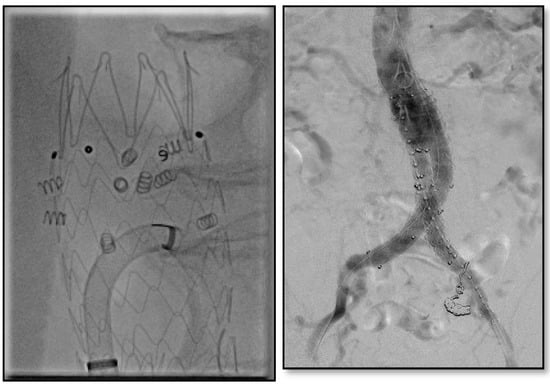

Physicians in our institution have utilized endoanchors prophylactically for hostile necks (Figure 4) and in those necessitating revisions for proximal neck dilation (Figure 5) or concern for type Ia endoleaks.

Figure 4. Juxtarenal abdominal aortic aneurysm with significant angulation treated with prophylactic endoanchors during index procedure.